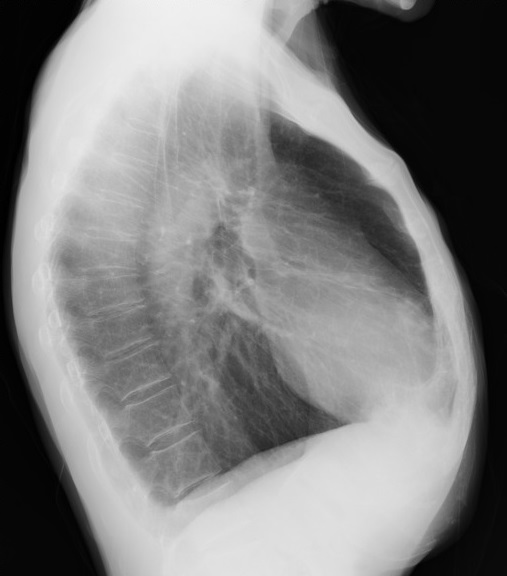

Image radiologique analogue du pectus excavatum

sur plain film PA / AP pulmonaire :

Image

radiologique analogue du pectus carinatum sur plain film PA /

AP pulmonaire :

-

Augmentation du diametre antero- posterieure du thorax

Deformation en deux forme : forme chondrogladiator (

angle de prostruction est en inferieure du sternum } et

chondromadibrual ( angle de prostruction est en

superieure du sternum }

radiologique TDM et IRM du pectus excavatum et carinatum :

Index Haller ( diametre

transverse maximale / diametre antero-posterieure du

thorax sur deux plain film AP et profile ) est de plus

3.25 en cas pectus excavatum . Nomalement etre de

moindre de 2 .

Angle de torsion du sternum

de plus 30 degree est egale d'agravation du pectus

excavatum

Indice de corection ( IC )

du thorax normale est 10 . De moindre est pectus

excavatum ..